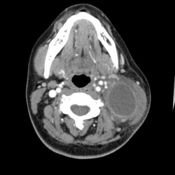

For esophagus cancer survival rates stage differs from early to late levels. There are three factors involved to determine the stage and its survival rate. The first factor is due to the tumor size and how far the cancer has spread in the esophagus. Another one would depend whether the cancer has spread in the nearby lymph nodes or not. Lastly, the stage depends on if the cancer has spread to other major body organs. Always remember that esophagus cancer positively depends on one or a combination of these three aspects. It is also important to know that esophagus cancer is limited to the inner layers of the esophagus and progressively moves outwards at higher stages. Preventing this cancer is what must everyone needs to do.